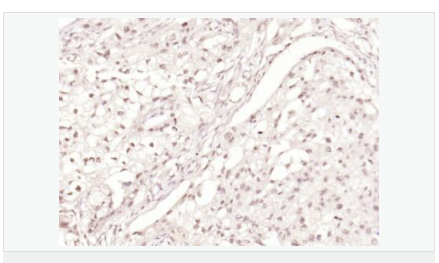

交叉反應:Human,Mouse,Rat(predicted:Pig,Cow,Horse,Rabbit,Sheep) 推薦應用:WB,IHC-P,IHC-F,ICC,IF,Flow-Cyt,ELISA

| 產(chǎn)品應用 | WB=1:500-2000 ELISA=1:5000-10000 IHC-P=1:100-500 IHC-F=1:100-500 Flow-Cyt=1μg/Test ICC=1:100 IF=1:100-500 (石蠟切片需做抗原修復) not yet tested in other applications. optimal dilutions/concentrations should be determined by the end user. |